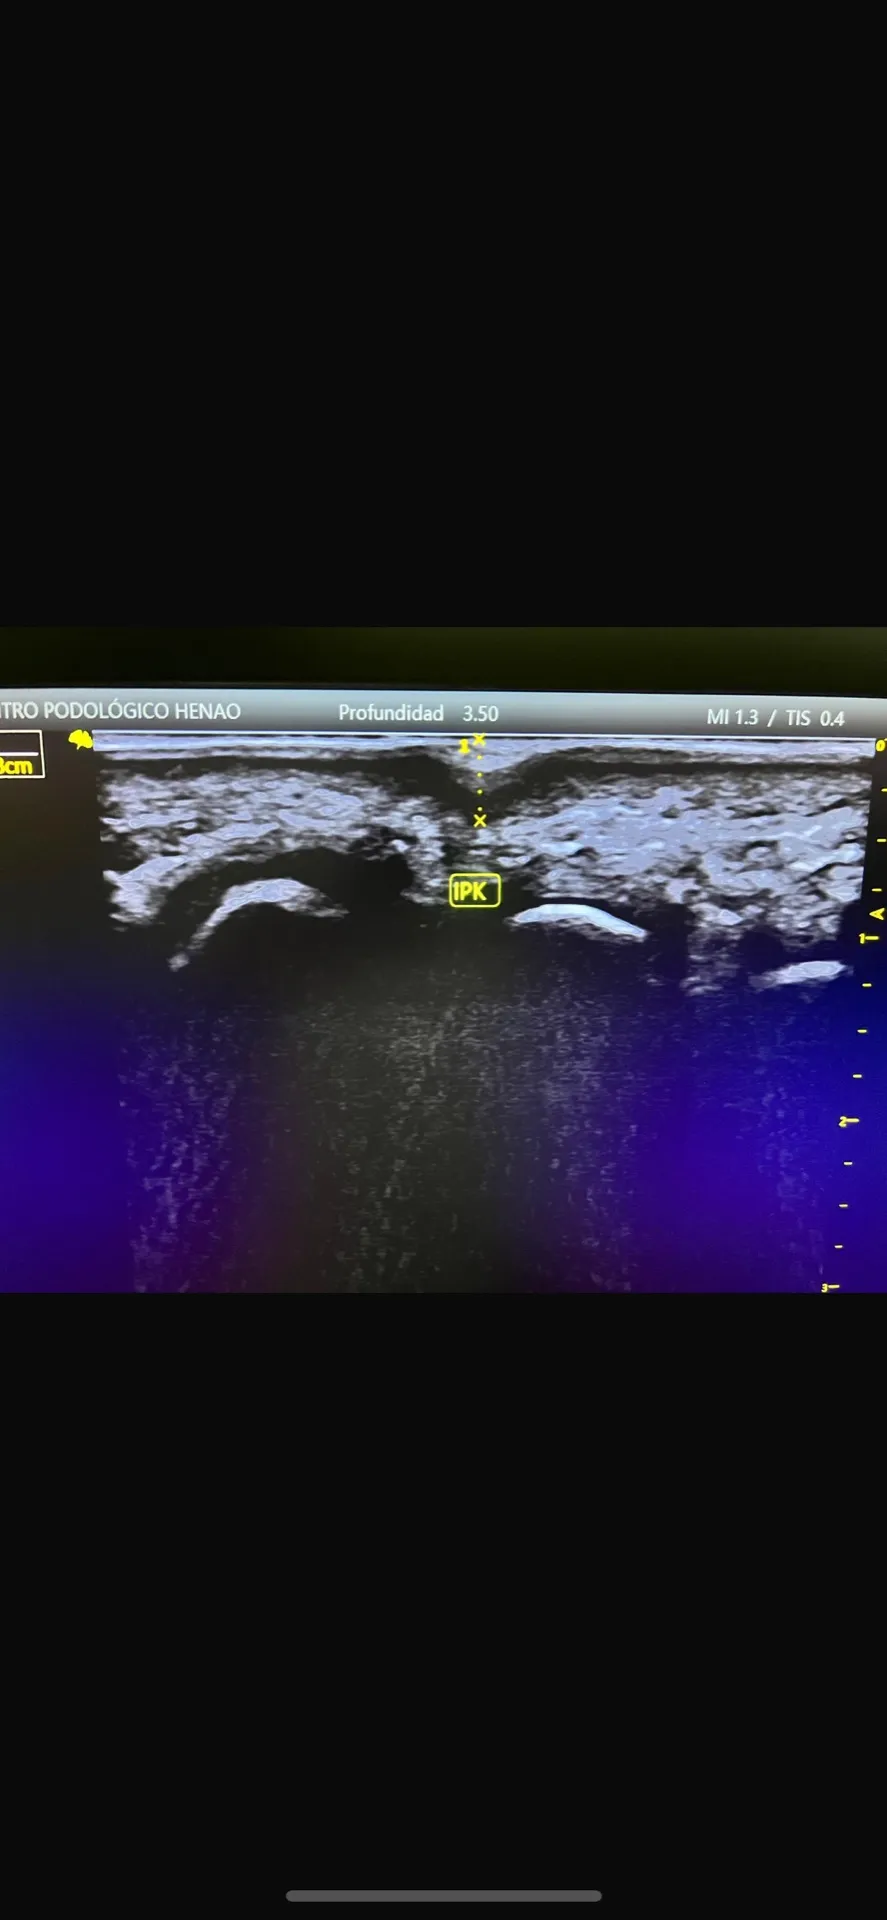

Pero no nos quedamos solo en la exploración visual. Utilizamos ecografía diagnóstica para valorar la localización exacta de las lesiones, su profundidad, características tisulares y vascularización. Estos datos son esenciales para el diagnóstico diferencial y para planificar el tratamiento más adecuado.

Figura 6: El estudio ecográfico nos permite ver estructuras que no son visibles a simple vista y planificar el tratamiento con precisión.

- Estudio ecográfico: Valoración de profundidad y características tisulares